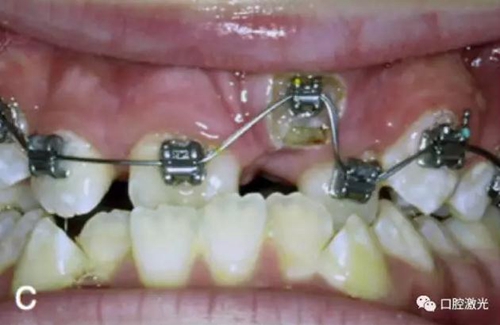

相比之下,激光開窗導(dǎo)萌有很多優(yōu)點(diǎn),如果有足夠的角化組織,那么是可以采用激光進(jìn)行開窗手術(shù)實(shí)施導(dǎo)萌,并立即粘接托槽。因此,同樣可以節(jié)省患者的等待時(shí)間。另外,口腔激光的止血特性可以提供清晰的視野,也有助于術(shù)后立即粘接托槽。

治療前

激光牙齦切割后即刻

粘接托槽

3周后效果